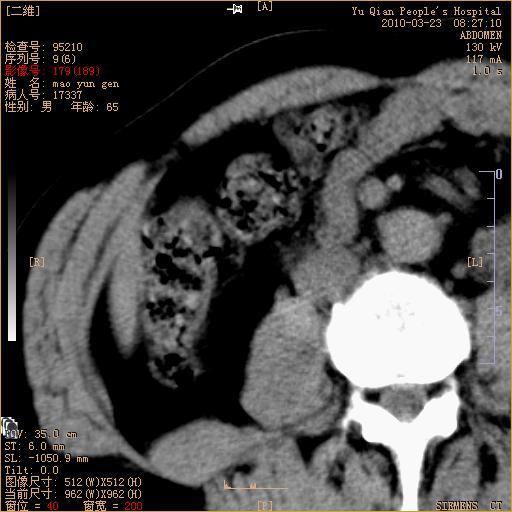

标题: CT25266:消瘦月余,前来肝部检查,请看看肠腔 [打印本页]

标题: CT25266:消瘦月余,前来肝部检查,请看看肠腔

升结肠肠壁增厚,不均强化,考虑升结肠腺癌可能性,建议肠镜检查。

1)考虑升结肠癌。2)右肾小囊肿。